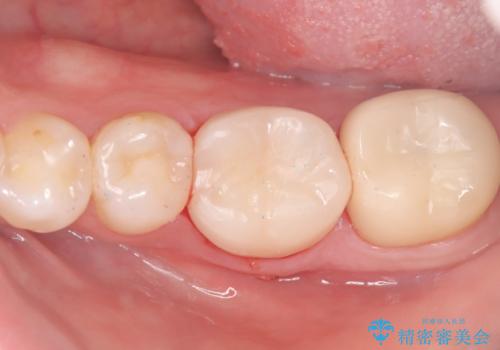

保存が難しい左下6番目の歯を抜歯し、左下8番目の歯(親知らず)を抜歯窩に移植しました。歯牙移植後の動揺防止のため暫間固定を行っています。

骨との定着を確認し、今後矯正治療を行う予定のためレジン冠をセットしています。